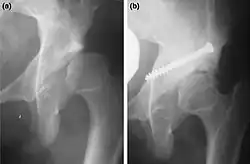

a. X-ray of a hip after capsulorrhaphy and Dega surgery.

b. Same hip after addition of Chiari medial displacementosteotomy.[4]

Two main types of osteotomies are used in the correction of hip dysplasias and deformities to improve alignment/interaction of acetabulum – (socket) – and femoral head (femur head) – (ball), innominate osteotomies and femoral osteotomies. The bones are cut, reshaped or partially removed to realign the load-bearing surfaces of the joint.[3]

Adjustments are made to part of the hip-bone. Many operating methods and variations have been developed. They are defined by the type of cut and adjustment made. Some acetabular procedures are named after the surgeons who first described them as Salter (R. Salter), Dega (W. Dega), Sutherland (D.H. Sutherland), Chiari (K. Chiari): other names one may encounter are Ludlov, P. Pemberton, and James B. Steele. Some are named after the shape of cut (e.g. Chevron, Wedge) or the way the bones are aligned (Dial=old style rotary dial phone).